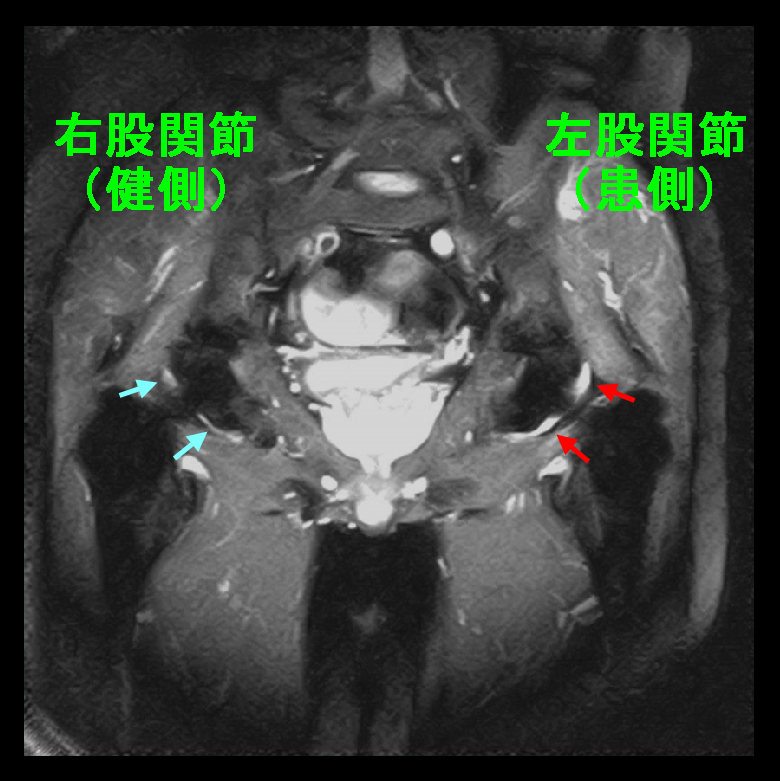

8月24日(3か月後)左手掌部痛で受診されました。以前は右手掌部痛でした。この時も左手根管ブロックを施行しています。この際、少し前に仕事中に右股関節痛で動けなくなり、救急搬送となり総合病院に入院したという報告がありました。9月21日右手掌部痛で受診。9月9日にも左股関節痛で総合病院に救急搬送、1週間入院加療したとのことでした。私が「総合病院の整形外科医師の診断はどうでしたか」と聞くと、「運動不足だからでしょう」と言われたとのこと。私は呆れてしまいましたが、患者さんも納得はしていませんでした。

56才男 MR2.jpg

その時の股関節のMRI所見ですが、左股関節は関節炎(赤矢印)を認めます。ここでもう1度リウマチの採血をしていますが、RF27(正常15以下)、抗CCP抗体53.5(正常4.5以下)で、患者さんもここからはメソトレキセートによるリウマチの治療をすることに同意されました。